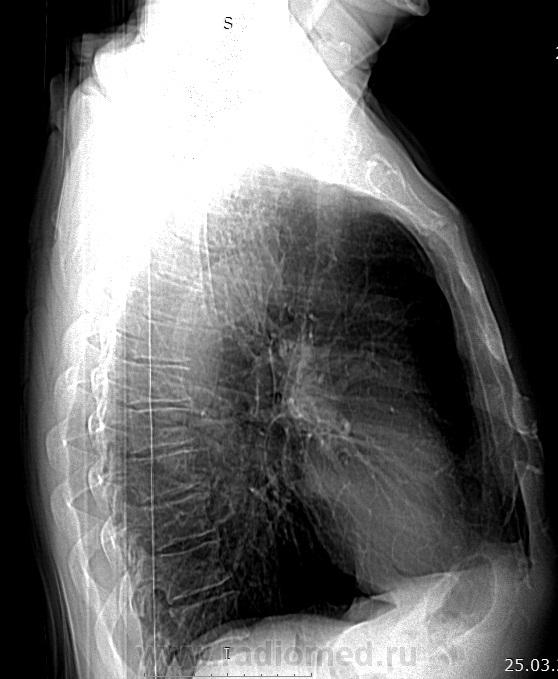

65 лет. Вич - отрицательный. Выявлен при проверочной флюорографии. Последняя флюорография в 2011 г. На контрольное обследование пациента не вызывали. Исходных данных не имею. Жалоб нет. Гемограмма в норме. Выполнена  КТ  органов дыхания. Предполагают туберкулёму, периферический рак? Прошу коллег высказать мнение о возможной природе выявленных изменений. Очень жду. C уважением Nikolas. Ссылка на дайком

Судя по КТ-картине в S1 имеется туберкулема прилегающая к костальной плевре диаметром 2,5см, а вокруг уже имеются мелкие очаги отсева в S1,2 сегментах...

Развил бы "мелкие очаги отсева" в очаговый туберкулез в верхней доле правого легкого в фазе инфильтрации.

Периферический рак никаким боком.

Коллеги. Госпитализирован в ПТД. Буду следить за динамикой процесса в легких на фоне лечения.